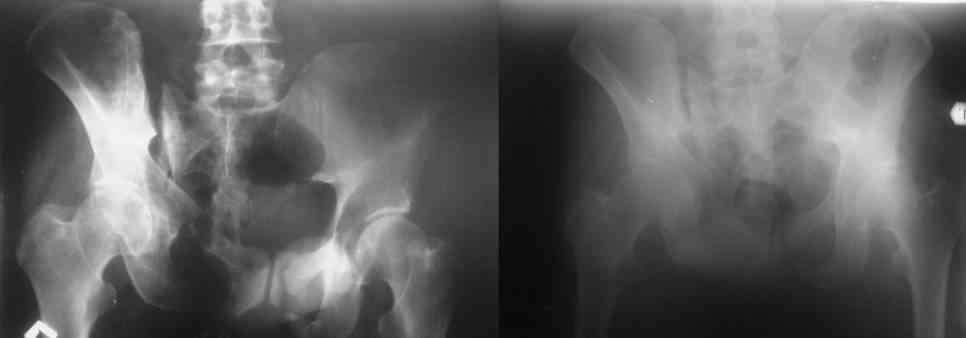

Re: Застарелое повреждение таза

Остается только вариант закрытого аппаратного лечения. В аттаче положение отломков на вытяжении в прямой (АР) проекции. Для сравнения снимок до и во время вытяжения.